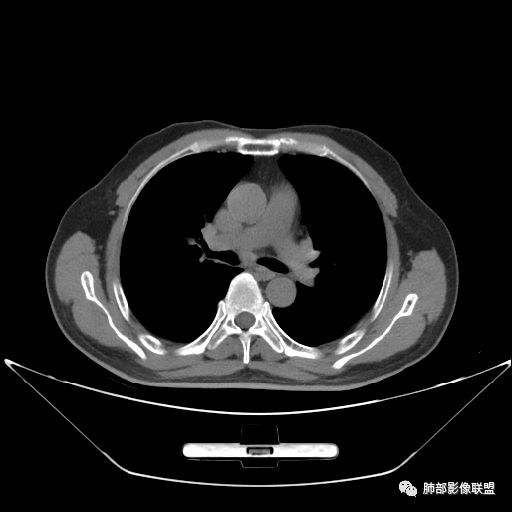

住院4天后行胸部增强CT

动脉期

老年男性,因“咳嗽咳痰1月余。”入院。病程中咳嗽咳痰,咳黄白痰,间断咯少许鲜红色痰血。PPD阳性。胸CT:右肺中叶外侧段支气管管腔阻塞,大片实性病变,病灶边缘光滑,部分边缘膨隆,可见分叶,肺门及纵隔可见肿大淋巴结,并可见钙化。增强可见病灶明显强化,而且延迟强化明显,病灶内多发低密度区,内见血管影,血管变细、部分血管破坏。考虑恶性病变可能性大,鉴别慢性肉芽肿性病变。

胸CT:跨叶大肿块,主体在中叶,右中叶外侧段支气管阻塞,病灶部分边缘膨隆,可见分叶,部分边缘平直,肺门及纵隔可见肿大淋巴结。增强病灶不均匀强化,延迟强化明显,病灶内多发低密度区,内见血管飘浮,部分血管变细、模糊。考虑:恶性病变可能性大,大细胞?淋巴瘤?鉴别慢性肉芽肿性病变。

右肺中叶软组织肿块,外围向内生长,叶间胸膜向前内移位,肿块近肺门侧跨叶,中叶外侧段支气管截断,密度不均匀,双侧肺门及隆突下见肿大淋巴结,增强后呈中度不均质强化,肺动脉供血,多发坏死区,边界尚清,坏死区域内见结构,结合病史考虑恶性,鉴别诊断1结核,爬行征是沿支气管树分布,外宽,内窄,周围有卫星灶,内气管狭窄后扩张,此例沿叶间胸膜长轴分布,气管有截断,不典型。2炎性肉芽肿,符合的地方下方层面增强后延迟性轻度环形强化,不符临床无发热等急性感染病史,实验室指标不符,病灶周围渗出及慢性炎性改变有,不明显。